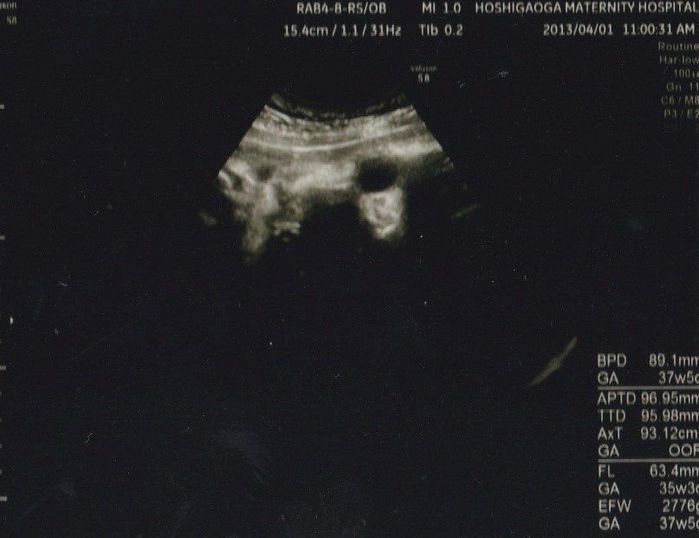

妊娠36週目のエコー写真

出産前最後のエコー写真です。全体的に黒くて何が写っているのかわかりづらいですが、黒い丸い部分が目で白い部分が鼻なような気もします。推定体重は2776g、ビッグベイビーだった長女と比べると少し小さめでした。2週間後にはこの腕で抱けると思うと、その日が待ち遠しかったです。長女と一緒に忙しい毎日を過ごしていた9ヶ月はあっという間に感じられました。